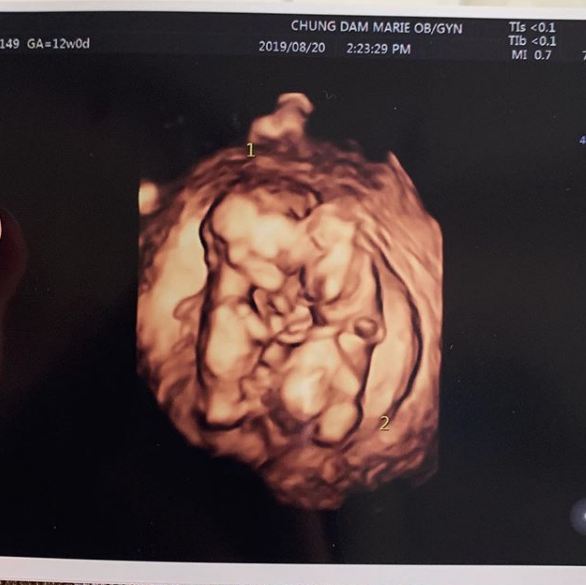

28일 율희는 자신의 인스타그램에 "짱이의 쌍둥이 동생들 소식듣고 많은 분들께서 축하해주셔서 감사하다"라며 초음파 사진을 공개했다.

둥이들은 이렇게 서로 꼭 붙어 잘 크고있답니다. 다시한번 축하해주셔서 감사드려요